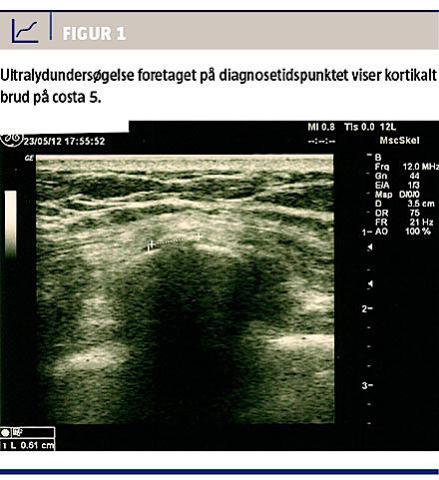

En ultralydundersøgelse af området for smertemaksimum viste et kortikalt brud uden synlig callus i tilhæftningen af serratus anterior på costa 5; dette

tydede på en nytilkommet skade (Figur 1).